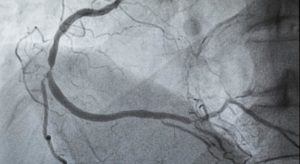

Was ist eine Herzkatheteruntersuchung?

Wenn Sie sich fragen, was eine Herzkatheteruntersuchung ist und ob diese für Sie oder einen...

Was ist eine Angiographie?

Wenn du dich fragst, was eine Angiographie ist und warum dieses bildgebende Verfahren für die...